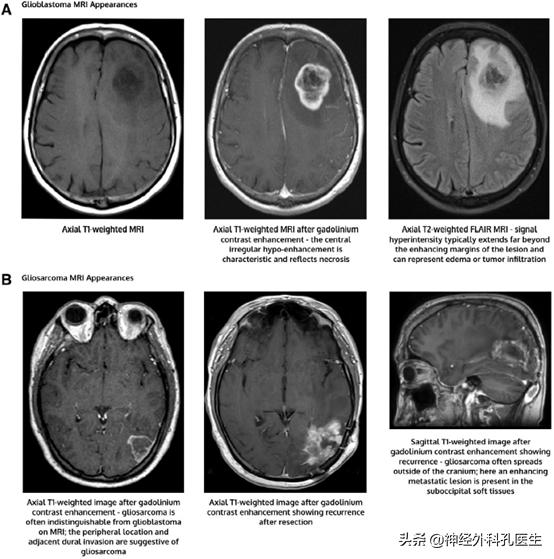

在组织学上,这两种类型的胶质母细胞瘤的特征仍然是高级别星形细胞瘤,其中包含微血管增生区域和/或局灶性坏死(图1)。

然而,在IDH野生型胶质母细胞瘤中,也存在一些特定的组织学变异。巨细胞胶质母细胞瘤包含大的、高度多形性的、多裂的巨细胞。胶质肉瘤呈交替区域,具有恶性星形细胞特征和肉瘤样间质上皮化生。最后,上皮样胶质母细胞瘤是一种新的变异,其特征是肿瘤细胞具有明显的上皮样形态。这种变异值得关注的是,携带BRAF V600E突变的比例很高(约一半)。然而,目前的治疗建议并不因组织学的不同而不同。胶质母细胞瘤和胶质肉瘤的特征性MRI表现如图1所示。巨细胞胶质母细胞瘤或上皮样胶质母细胞瘤的影像学特征不能可靠地区分这些肿瘤。